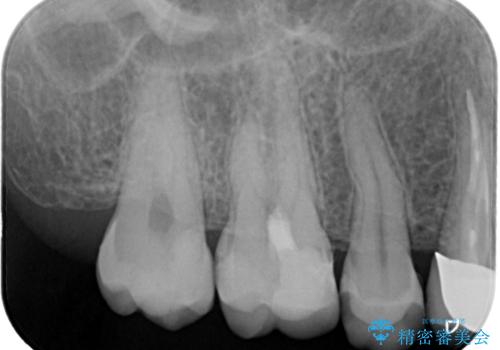

- 虫歯が大きく神経まで達していたので、VPT(歯髄温存療法)を行って細菌感染した部分の神経のみ取り除き、保存可能な神経は保存し被せ物はセラミックインレーで治療を行いました。

昔の歯科医療では神経まで虫歯が達している場合は神経を全て取らなければいけませんでした。しかし現代の歯科医療ではBio-C SealerやMTAセメントの開発により健康な神経を残せるようになりました。

※術前に神経の状態の検査を行い、術中にもマイクロスコープにて神経の状態を直接確認したうえで残せると判断した場合に行っています。